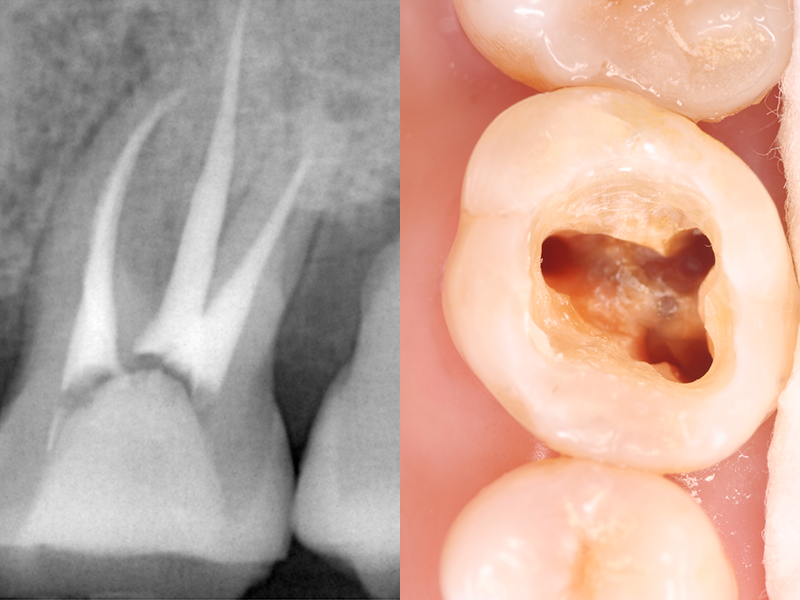

歯の内部には、神経や血管を含む「歯髄(しずい)」と呼ばれる組織があります。

虫歯の進行や外傷によって、この歯髄が細菌に感染したり、壊死したりした場合には、「根管治療」によって歯髄を除去する必要があります。一般的に「神経を抜く治療」と呼ばれています。

感染した歯髄や血管をそのまま放置すると、炎症が広がり、抜歯のリスクが高まります。根管治療では、感染した部分を丁寧に除去し、洗浄・消毒を行うことで、歯を抜かずに残せる可能性が高まります。

虫歯菌に侵された根管内にある神経や血管を除去し、消毒のための薬剤を充填してから補綴物(ほてつぶつ)を装着することで、歯根を残す治療方法です。

根管治療用の器具を使い、感染している歯質や残っている歯髄などを除去します。